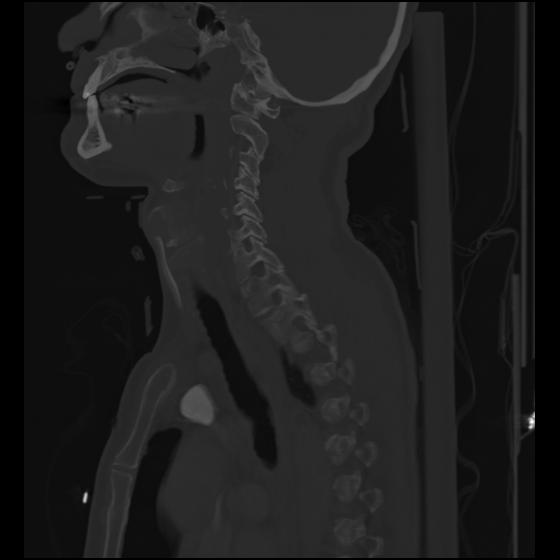

24 ANGIO,CE,Sag-MIP,5.000,ANGIO,Sag-MIP,